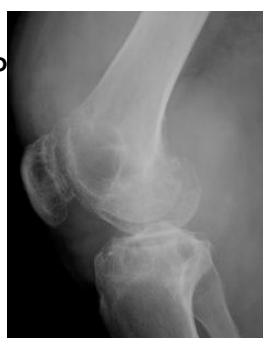

Giant Cell Tumor

Epiphyseal-Metaphyseal Lesions

Benign aggressive lesions:

- Giant Cell Tumor (GCT)